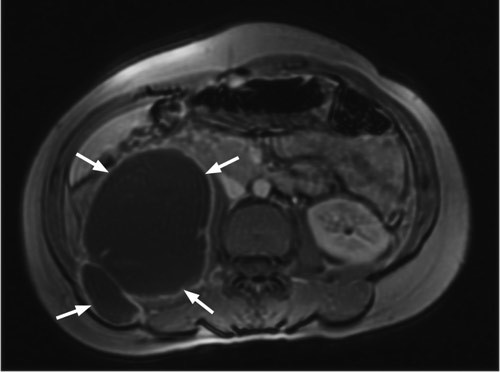

She had an erythrocyte sedimentation rate of 49 mm/h. Other general blood tests, including an HIV test, were normal. Both chest X-ray and urine culture for mycobacteria were negative. MR abdomen revealed findings as for spondylodiscitis at level Th11/Th12 with a large depression abscess in the right m.psoas (left). The abscess measured approximately 14 cm craniocaudally and extended caudally to the level of the L5 corpus vertebrae. A section through the abscess is seen on the right. Microscopy of the abscess material revealed no findings of acid-resistant rods. Culturing and polymerase chain reaction revealed findings of Mycobacterium tuberculosis. About 350 ml pus was drained off and long-term tuberculostatic treatment was started. The woman is being monitored regularly through outpatient follow-up.